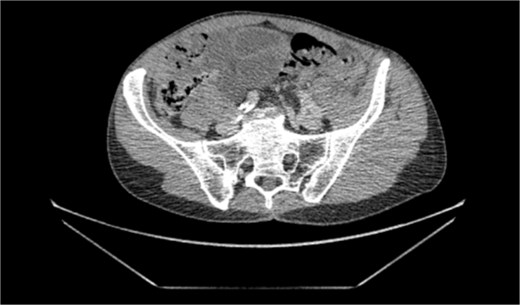

We present a case of a 76-year-old gentleman who had a previous elective laparoscopic TAPP right inguinal hernia repair in another hospital on January 2023. The procedure reportedly went well with no complications. The patient then presented on March 2023, 2 months after his procedure, with symptoms of small bowel obstruction. The initial computed tomography (CT) scan showed high-grade small bowel obstruction (Figs 1 and 2). The patient was initially treated conservatively as for most cases of small bowel obstruction thought to be attributed to adhesions from recent surgeries. The decision was made to take the patient for a diagnostic laparoscopy 48 hours after conservative management failed to resolve symptoms. Laparoscopically, gross small bowel ischemia was noted, and a tube-like structure was seen wrapping around the ischemic segment (Figs 3 and 4). The decision was taken to convert the procedure to an open one due to massive bowel dilatation and the inability to define the nature of this adhesive wrap. Upon conversion, it was noted that this tube-like structure causing the band was indeed the appendix wrapping around the terminal ileum, with its distal part adhered to the eroded mesh from the peritoneal flap of the recent TAPP repair. The decision was taken to perform a limited ileocecal resection and primary anastomosis. The protruding part of the mesh was excised, and the appendix resected. The peritoneal flap was closed with sutures. The patient did very well postoperatively and was discharged a couple of days later.

Transverse cross sectional view of mottled small bowel in the pelvis as a result of the closed loop obstruction.